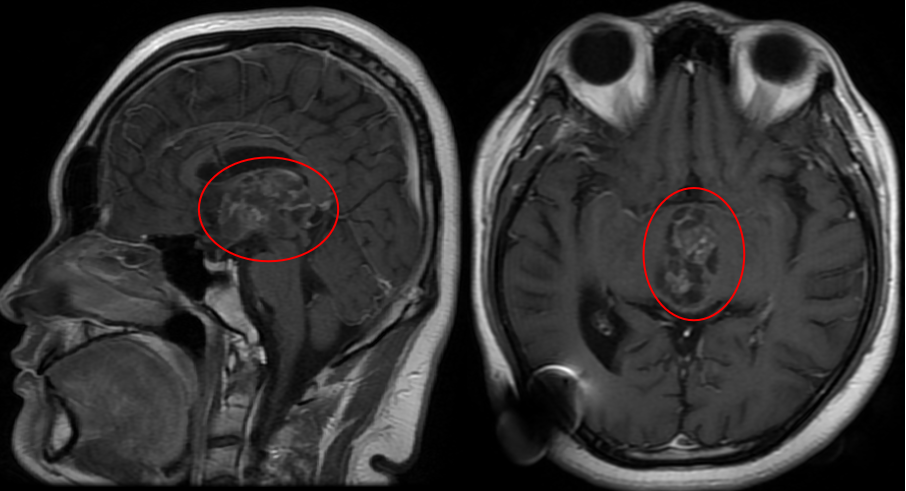

随后他们尝试过中医,可惜效果不彰。现实终究是残酷的:飞宇在长大,肿瘤也在长大。眼科检查出现复视,视力显著下降、视野缺损——MRI显示,一颗40毫米的巨大肿瘤已占据第三脑室,正悄然吞噬少年的未来。

术前MRI

“今年复查,肿瘤又长大了,不能再等。”这一次,他们没有丝毫犹豫。恰逢巴教授来华,从7月31日复查到8月12日手术,不过十余天。“其实我们从一开始就没打算找别人做。这是脑袋里的手术,我们必须给他最好的。”

这个40×25×31mm的巨大肿瘤已完全占据第三脑室,并从室间孔向下压迫中脑,使得手术面临重重挑战。首先,手术路径深长而狭窄,需要在切开胼胝体、分离脉络膜裂后,在受限的操作通道内精准切除肿瘤,对手部稳定性要求极高。其次,肿瘤已使关键的脉络膜裂发生扭曲、变薄,其与周围深部静脉系统和丘脑的粘连紧密,分离时极易引发出血或梗死。再者,肿瘤本身血供丰富且质地坚韧似橡皮膏,与三脑室壁、丘脑、深部血管黏连紧密,只能分块切除或借助CUSA,强行牵拉易导致出血或伤及周围结构。